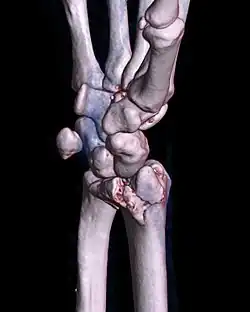

A palmar Barton's fracture of the right wrist, as shown on a 3D-rendered CT scan

A Barton's fracture is a type of wrist injury where there is a broken bone associated with a dislocated bone in the wrist, typically occurring after falling on top of a bent wrist.[1] It is an intra-articular fracture of the distal radius with dislocation of the radiocarpal joint.[2]

There exist two types of Barton's fracture – dorsal[3] and palmar, the latter being more common. The Barton's fracture is caused by a fall on an extended and pronated wrist increasing carpal compression force on the dorsal rim. Intra-articular component distinguishes this fracture from a Smith's or a Colles' fracture. Treatment of this fracture is usually done by open reduction and internal fixation with a plate and screws, but occasionally the fracture can be treated conservatively.[4]